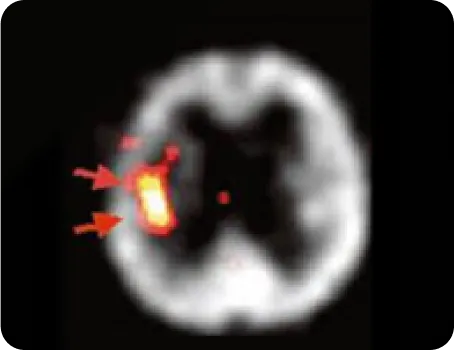

우측 중대뇌동맥 폐색 환자의 3주 후

SPECT(뇌 혈류 역학 검사) 사진

침 치료 8일 후 증가된 혈류

침 치료 후 증가된 뇌경색 주변부 혈류량